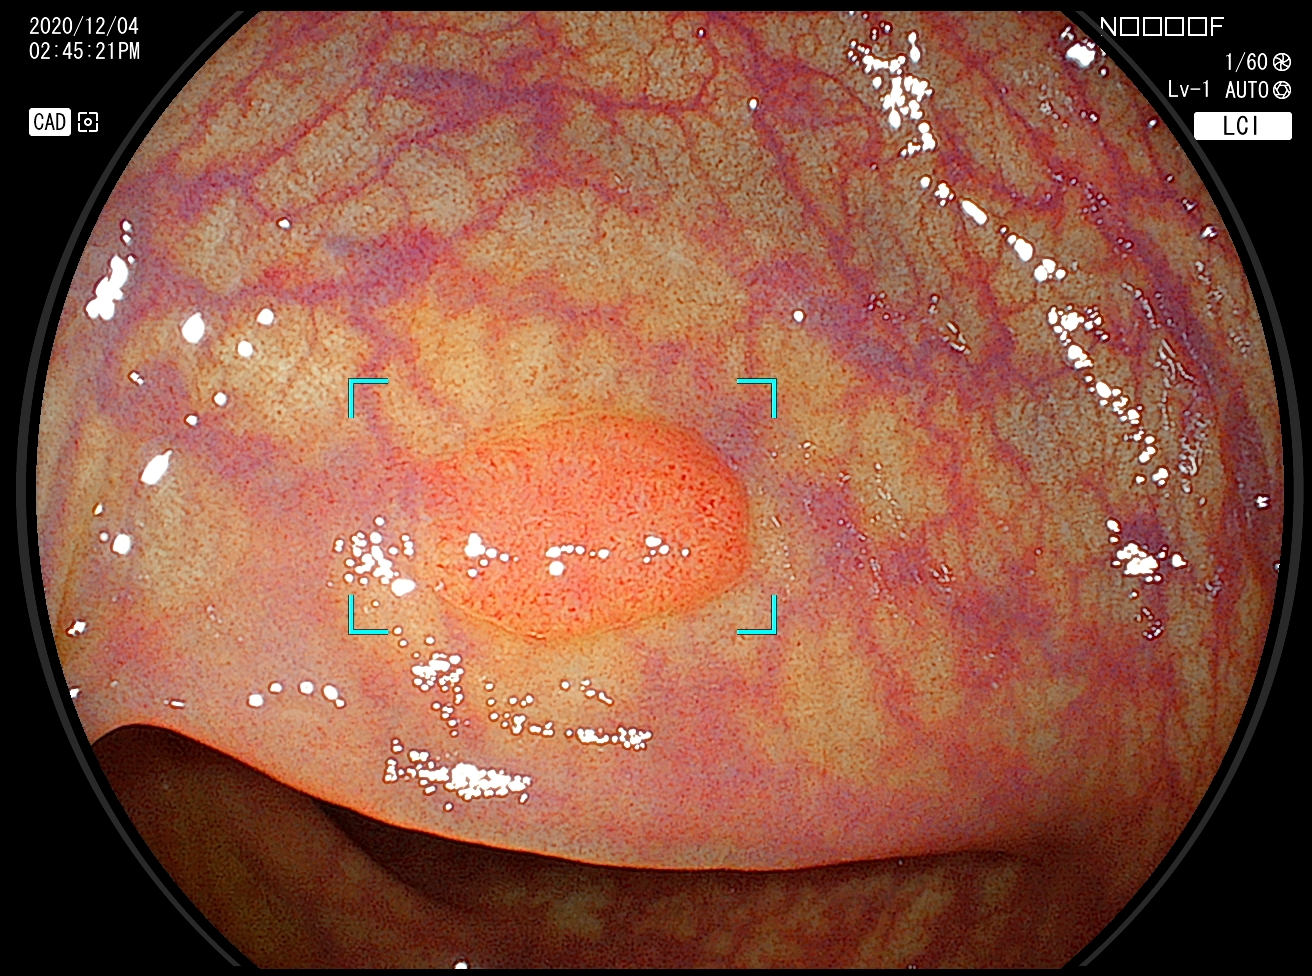

Proc202012010004_1_25